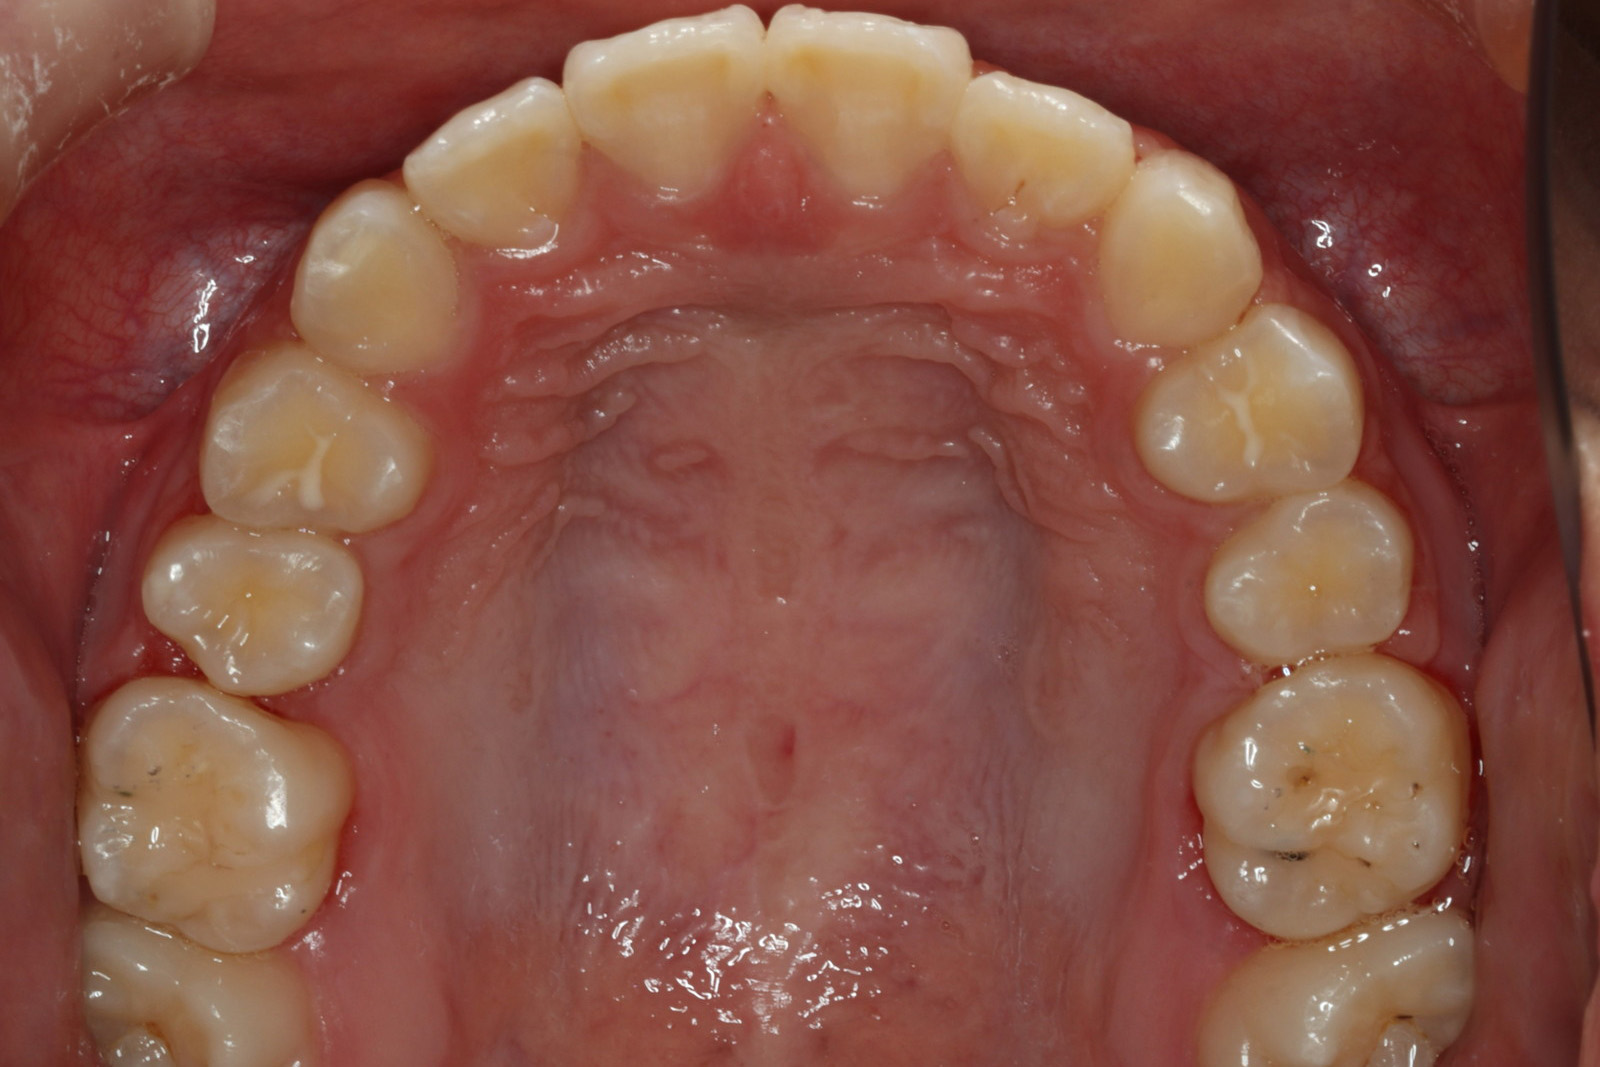

問診を行い、お口の悩みや希望を確認します。レントゲン撮影や口腔内写真の撮影など、必要に応じた精密検査を行います。